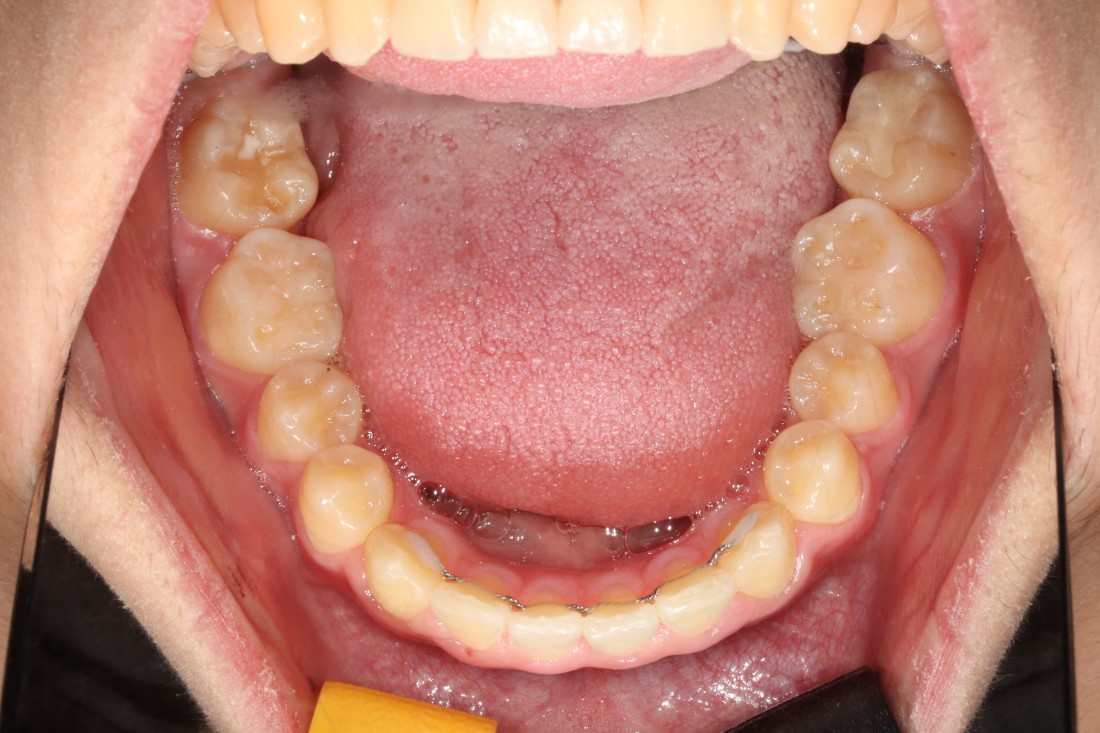

광주 덧니교정 치과는

대표원장인 제가 직접

다양한 교정 전/후 케이스를

공유하고 있습니다.

다양한 각도에서 촬영한

교정 전/후 사진을 직접 확인할 수 있어

광주 덧니교정 치과의

실력있는 진료를 증명하고 있습니다.

발치를 진행한 덧니교정이나

비발치 덧니교정 모두

다양한 케이스를 보유하고 있기 때문에

나의 구강구조와 비교해보면서

성공적인 교정치료 결과를

기대해보실 수 있습니다.